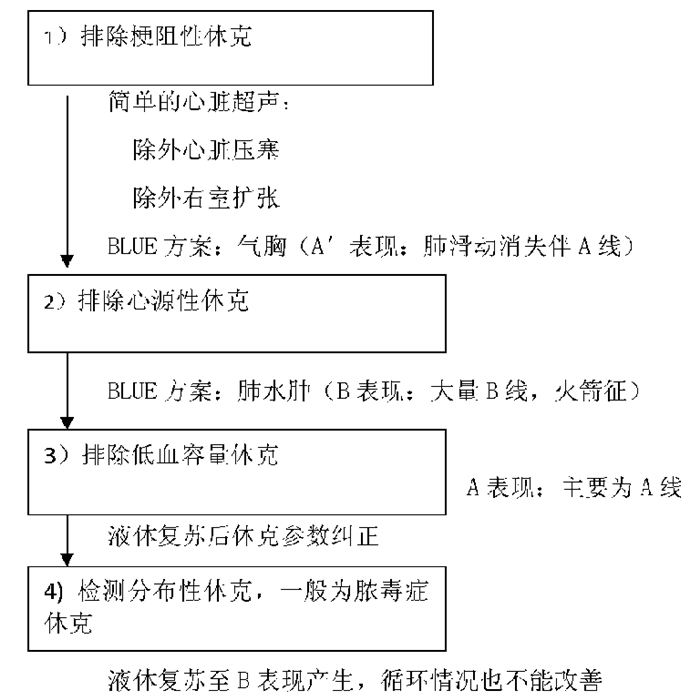

(2)FALLS草案[24]: 2015年,Lichtenstein在BLUE草案基础上制定了FALLS草案(图 35),用于处理急性循环衰竭患者。FALLS草案通过逐步排除梗阻性休克、心源性休克、低血容量性休克,从而确定分布性休克(常为脓毒性休克)的诊断。这些检查都可通过简单的便携式超声机和凸阵探头来完成。

| 图 35 FALLS草案 |